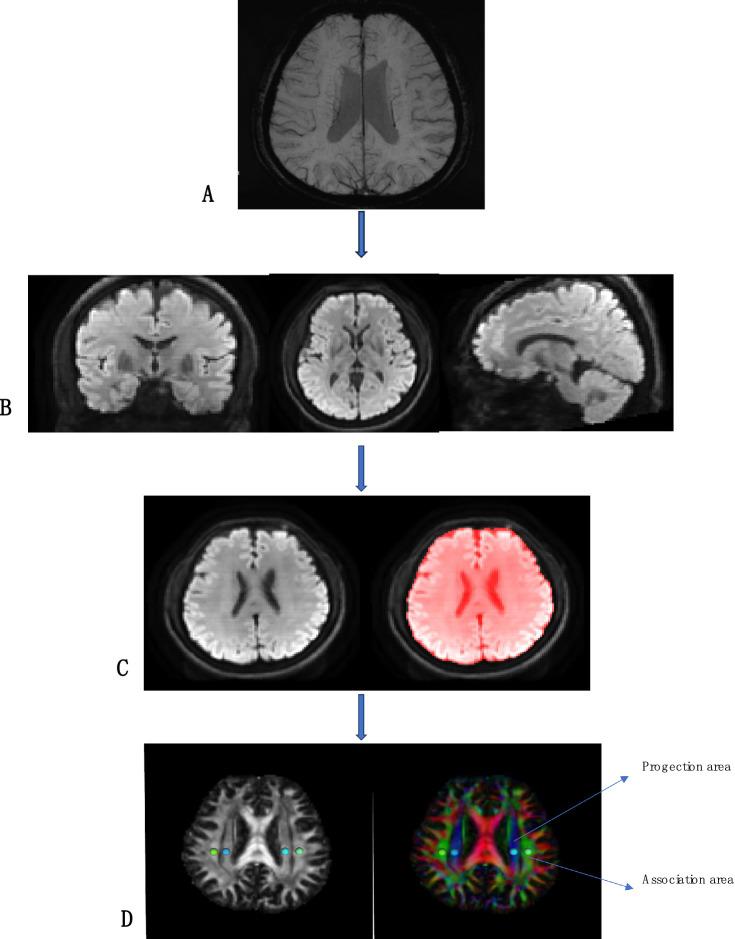

This study aimed to evaluate brain glymphatic function in COVID-19 recovered patients using the non-invasive Diffusion Tensor Imaging-Analysis Along the Perivascular Space (DTI-ALPS) technique. The DTI-ALPS technique was employed to investigate changes in brain glymphatic function in these patients and explore correlations with cognitive function and fatigue.

本研究旨在使用无创的沿血管周围间隙扩散张量成像分析(DTI-ALPS)技术评估新冠康复患者的脑类淋巴功能。采用DTI-ALPS技术研究这些患者脑类淋巴功能的变化,并探讨其与认知功能和疲劳的相关性。